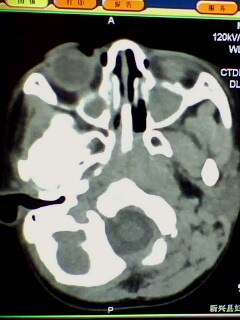

支持鼻咽增殖体肥大、双侧上颌窦炎。

1)鼻咽腺样体肥大。2)双侧上颌窦、双侧筛窦及双侧蝶窦炎症。

鼻咽增殖体肥大、双侧上颌窦炎。

鼻咽腺样体肥大,副鼻窦炎。